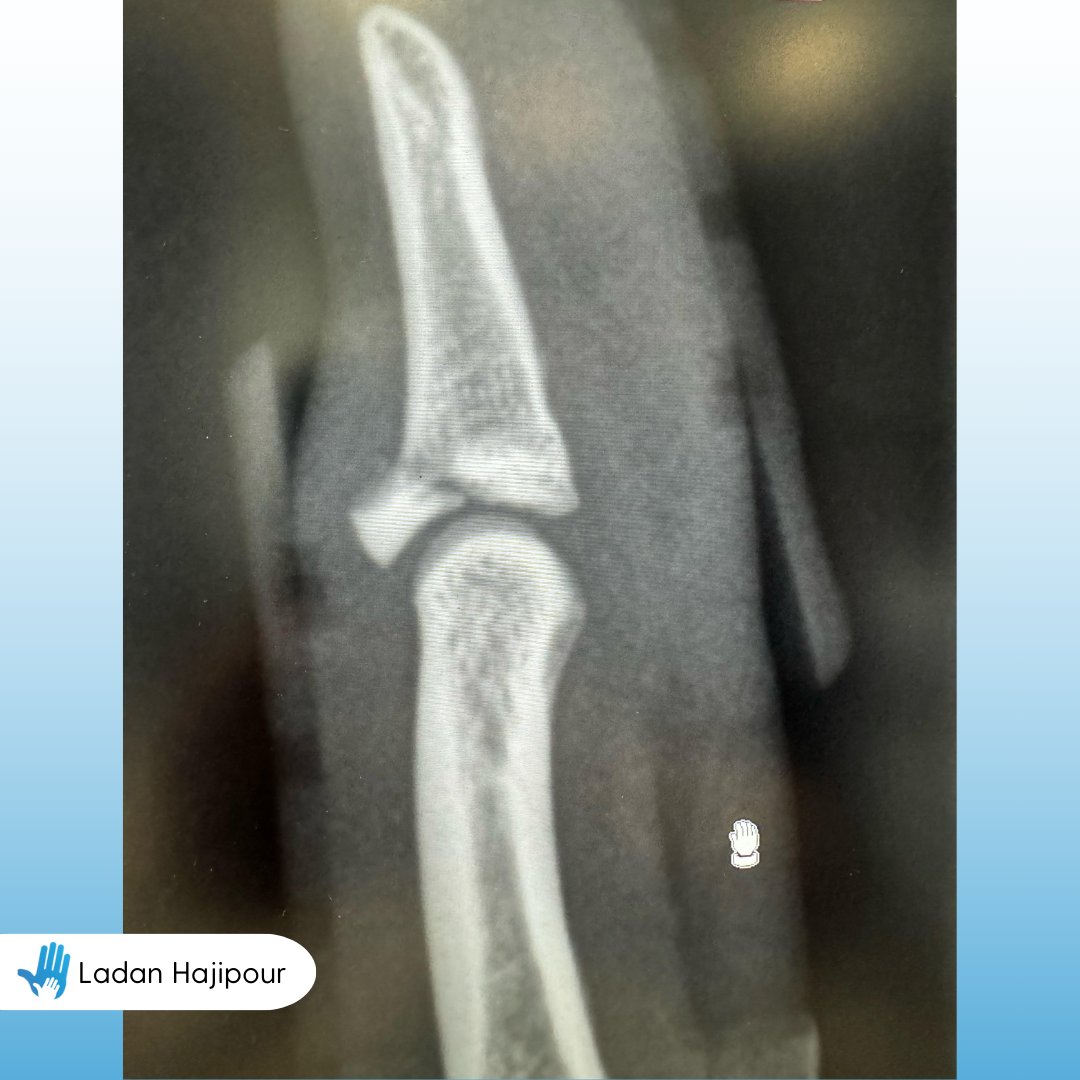

X-rays help your surgeon pinpoint the cause of pain, swelling, or tenderness in your hands and wrists. They’re essential for diagnosing conditions like fractures, dislocations, arthritis, carpal tunnel syndrome, and more. 🩻